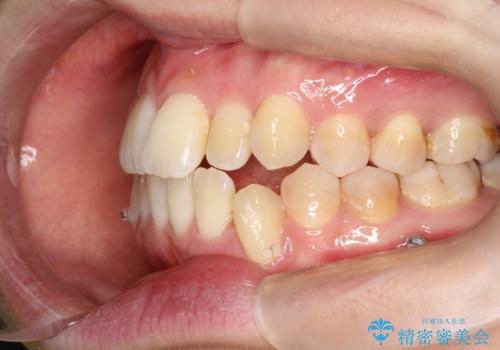

- 前歯のガタガタと、かみ合わせを改善したいとのことで来院されました。

人前でお話をするお仕事のため、装置をつけないでよいマウスピース矯正を希望されました。

下顎の歯が、上顎の歯に対して前方に位置していたので、下顎の歯を後方に移動させるのと、歯と歯の間を削りスペースを作り、歯を並べる計画としました。

お仕事の関係で使用時間が制限されるときもあり、治療期間が予想より少し長くなりましたが、装置をつけずに治療を終えることができました。